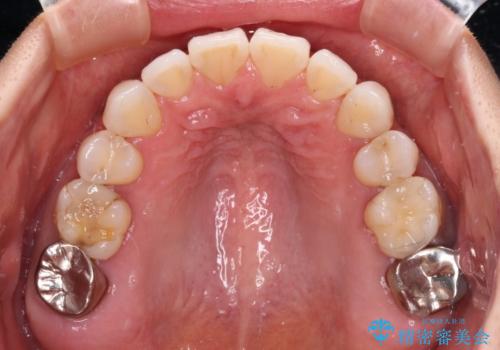

- 下顎前歯を中心に、以前行った矯正治療の後戻りが気になるとのことで来院された患者様です。

後戻りは軽度であったため、インビザライン・ライトにて治療を行うこととしました。